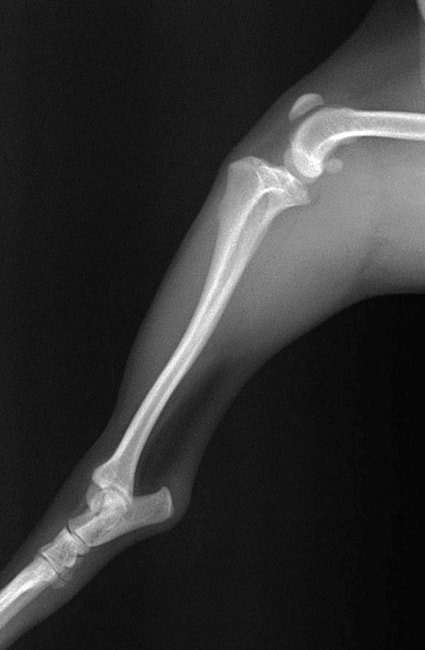

■ 症例24 キャバリア 7か月

左右膝蓋骨内方脱臼(左:グレードⅣ 右:グレードⅢ)

以前から左右後肢の跛行が認められ、整形外科学的検査・レントゲン検査により左右の膝蓋骨脱臼が認められた。症状が重度である左膝の膝蓋骨脱臼整復術を行った。外科手技は縫工筋及び内側広筋の解放、脛骨粗面の外側転位、滑車ブロック形造溝術、内外側関節方の縫縮を実施した。術後一か月時点で、左の膝蓋骨は安定しており経過は良好である。

本症例は成長期における重度の膝蓋骨脱臼であり、術後の再発の可能性もあるため、経過をしっかりと観察していく必要がある。また、今回手術を実施していない右膝に関しても経過を観察し、手術を検討していくこととする。